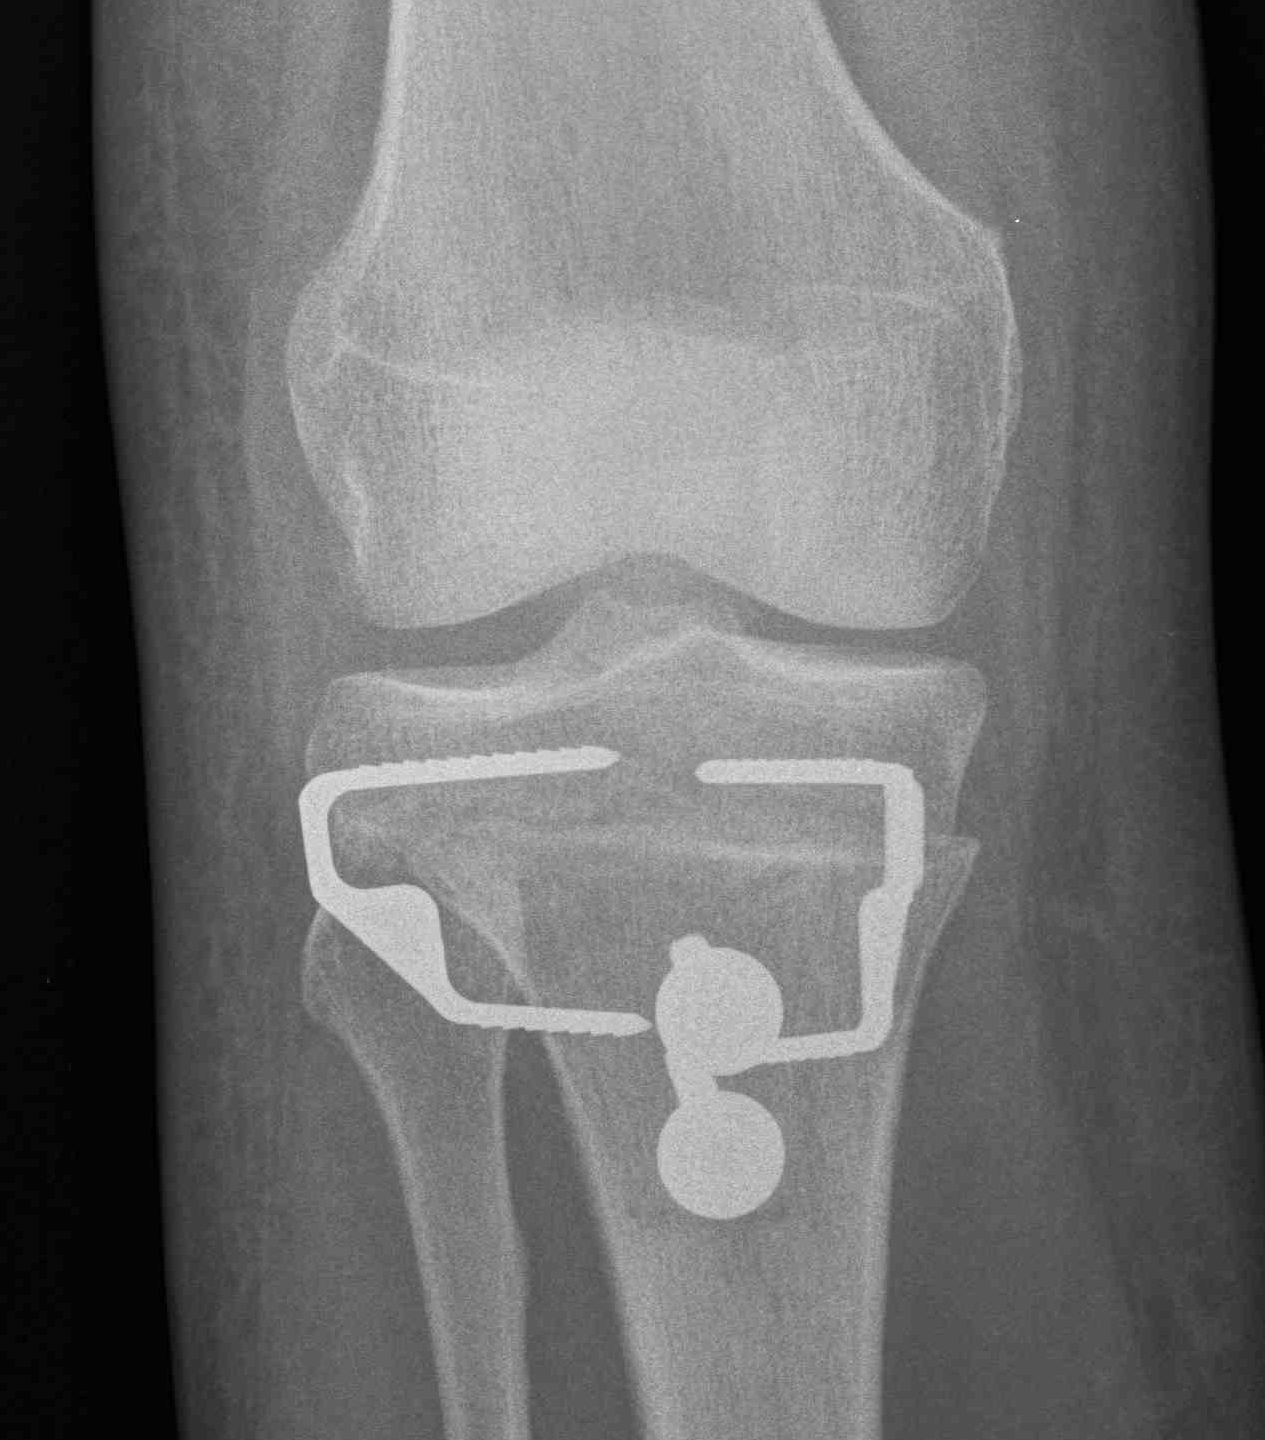

2. Perform TTT (if TTTG > 20)

- incision over TTT

- medialise at least 1 cm

- ensure some element of Fulkerson / anteriorise

- can distalise if patella alta

- secure with screws (2 x small fragment usually sufficient)

- reassess stability